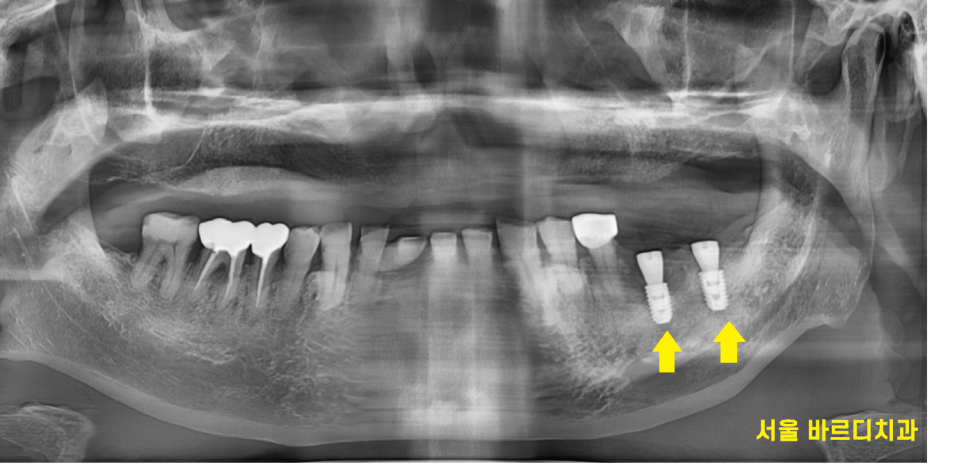

23.09.19

둔촌동 임플란트 예쁘게 수술이 되었습니다.